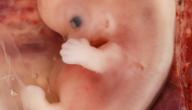

يبدأ نمو المخ عند الجنين في الأسبوع الثالث من الحمل، ويعادل الأسبوع الأول من عمر الجنين، ثمّ تبدأ أجزاء المخ المعقّدة بالتكون في الأسبوع السادس من الحمل، وهو ما يعادل الأسبوع الرابع من عمر الجنين، وفي حلول الشهر الثاني من الحمل يتكون المخ، حيث ينمو دماغ الجنين ليصل حجمه إلى نصف حجم الجسم، ثمّ يزداد نموّ رأسه وتبدأ عظامه بالتكوّن.

الجنين في الشهر الثاني من الحمل

يطرأ على الجنين في هذا الشهر عدة تغيرات، ومنها ما يلي:

- يبلغ طول الجنين في نهاية الشهر الثاني من الحمل حوالي 2.5 سم، كما يصل وزنه إلى 300 غرام.

- تبدأ أعضاء الجنين الداخلية بالتكون مثل: الدماغ، والكبد، والمعدة، والرئتين، كما تبدأ أذن الجنين الداخلية بالتكوّن.

- تبدأ أعضاء الجنين الخارجية بالتكون، مثل: الأجفان، والأطراف، والأصابع، والأعضاء التناسلية.